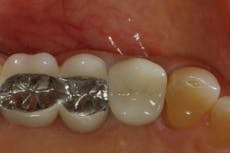

Approximately 12 weeks after healing, the area was inspected (Figure 5) and a new radiograph was taken to visualize the underlying bone. There was adequate width and height to place an implant that would replicate the premolar.

When the patient returned three to four months later, the healing cap was removed and impressions taken. Following the necessary lab procedures, the dental implant was restored with the final abutment and crown in place (Figure 6).

Fig. 5 — Healed ridge (5894)

Fig. 6 — Implant, abutment, crown (8466)